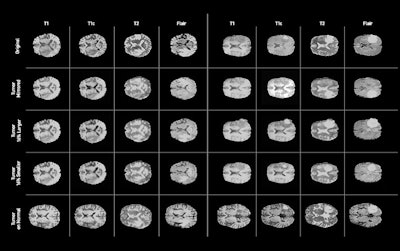

Examples of synthetic brain MR images generated by the GAN. The first row depicts the real images on which the synthetic tumors were based. The second row shows the generated images without adjustment of the segmentation label, while the third through fifth rows provide examples of generated images with various adjustments to the tumor segmentation label. The last row includes examples of synthetic images with a tumor label placed on a tumor-free brain MRI. Image courtesy of NVIDIA.The use of GANs in medical imaging has been on the rise lately for applications such as creating a synthetic head CT image from a brain MR image and for producing synthetic x-ray images to aid in algorithm training. In their project, the researchers trained a GAN using the Alzheimer's Disease Neuroimaging Initiative (ADNI) dataset and the Multimodal Brain Tumor Image Segmentation Benchmark (BRATS) dataset.

The algorithm allows developers to alter the size of a tumor on the MR image, change its location, or place it on an otherwise normal brain -- enabling hundreds or even thousands of these synthetic images to be created, according to the researchers. In testing, they found that adding synthetic data to augment real MRI data improved the performance of a deep-learning algorithm.